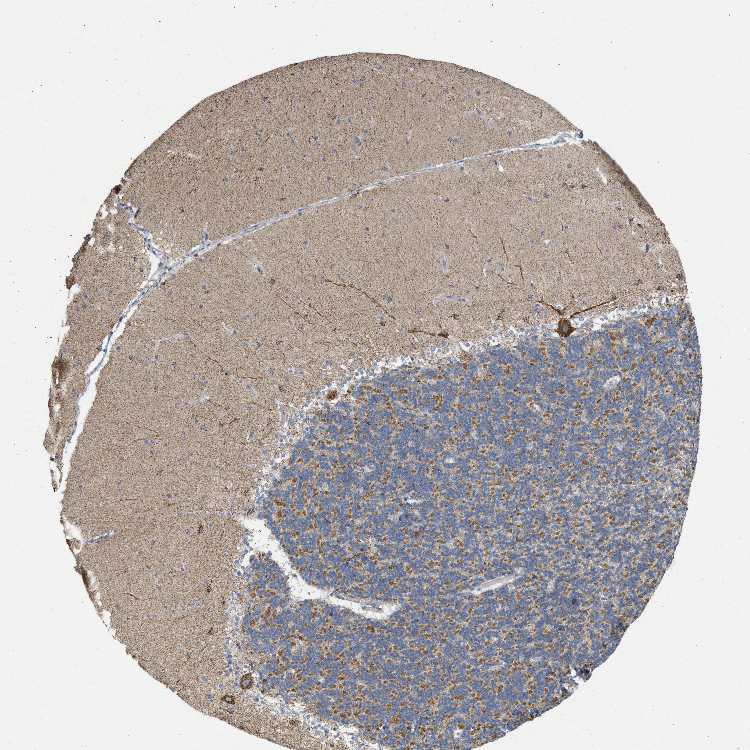

BRAIN CEREBELLUM Show tissue menu

CEREBELLUM - Expression summary

CEREBELLUM - Antibody stainingi

Antibody staining in the annotated cell types in the current human tissue is reported as not detected, low, medium, or high, based on conventional immunohistochemistry profiling in selected tissues. This score is based on the combination of the staining intensity and fraction of stained cells.

Each image is clickable and will lead to virtual microscopy that enables deeper exploration of all samples and also displays staining intensity scores, fraction scores and subcellular localization as well as patient and tissue information for each sample.

Antibody HPA027502Antibody CAB019423

Purkinje cells LowHigh

Cells in granular layer Not detectedMedium

Cells in molecular layer MediumMedium